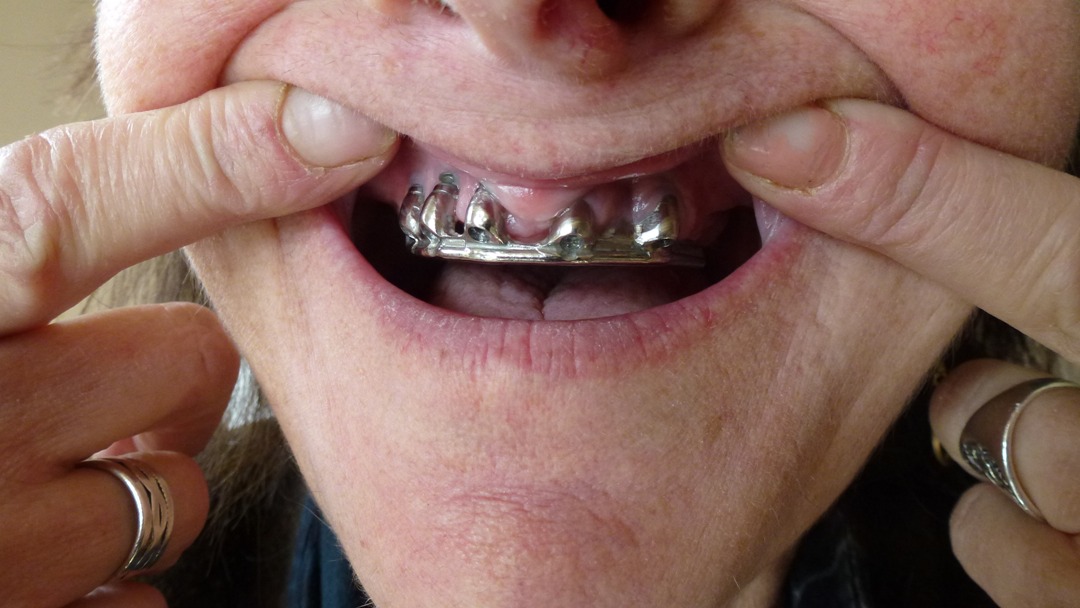

- 5eme cas Madame sylvie Sal qui à reçue une prothèse complète en 2009 chez ………..(oui, c’est bien l’intermédiaire qui m’a indiquer cette clinique, année 2009 en été)En février 2013 elle demande un double de sa radio ………….. Auprès du secrétariat on lui a répondu, qu’un problème informatique est survenu dans leurs système! Plus de radio! de madame Sal pour faire un contrôle ultérieur. Il ne fond pas de radio, ou ils les perdent…les implants du bas on du être enlevez d’urgence en Février 2013 par sont dentiste en France dans le Luberon … Vous pouvez voir état de sa bouche. Publier avec l’autorisation de la patiente.Bonjour,Voilà c’est a cela que ça ressemble, je trouve qu’il y a une différence de couleur.

Celle du gars sont plus grise, les miennes sont plus brillantes….. joli n’est ce pas?? impressionnant!

Et celles du bas ne sachant plus les enlever, tant ça me fait mal…donc rien à vous montrer

Bien à vousSylvie